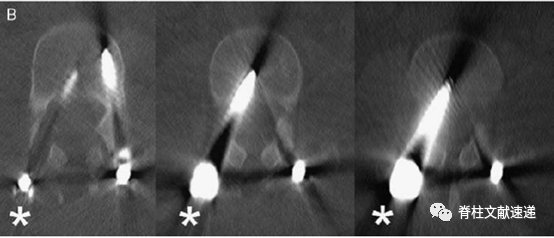

Kim等人定义椎弓根螺钉误置标准为突破皮质0 ~ 2mm(轻度、安全)、2 ~4mm(中度、可能安全)、>4mm(重度、不安全)。

触发式肌电图(t-EMG)阈值为>10mA的螺钉被认为位置良好。当阈值<10mA时,取下螺钉,修改椎弓根轨迹,并根据椎弓根内壁情况来定。该技术不会显著延长手术时间,可以有效防止神经系统并发症的发生,应该被推荐。

>15mA,螺钉在椎弓根内位置的可信度为98%;

10-15 mA, 螺钉在椎弓根内位置的可信度为87%;

<10 mA, 90%的病例出现皮质破裂。

Calancie等描述了刺激诱发(触发)肌电图(EMG) 技术,对工具或螺钉进行电刺激,测量受刺激器械附近的神经根支配的肌肉动作电位。测量值低于设定阈值的低刺激电流引起的肌肉动作电位,理论上表明骨皮质破裂或手术器械接近神经根。

tEMG检测椎弓根螺钉误置的总体敏感性为0.78,特异性为0.94。tEMG电流阈值为10-12 mA和脉冲持续时间为300 微秒,提供了最准确的测试参数,椎弓根螺钉的肌电信号最为准确。